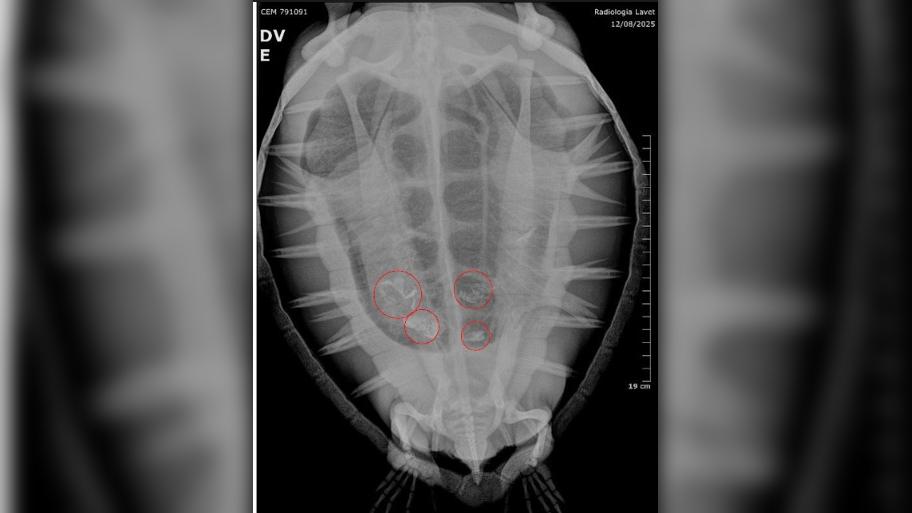

Durante o inverno, período em que aumenta o número de encalhes de animais migratórios, a equipe do PMP-BS registrou casos de tartarugas com ingestão de resíduos.

“Infelizmente, acabamos atendendo vários animais marinhos com plástico, tanto fragmentos rígidos quanto embalagens maleáveis. Já tivemos casos em que o animal chegou vivo ao CReD, mas não resistiu”, afirmou a médica veterinária Carolina Jorge.